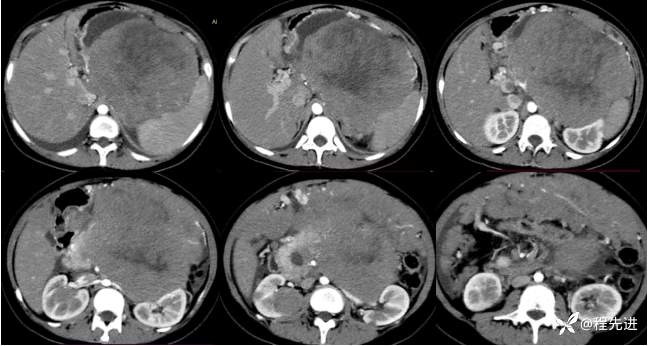

增强早期: